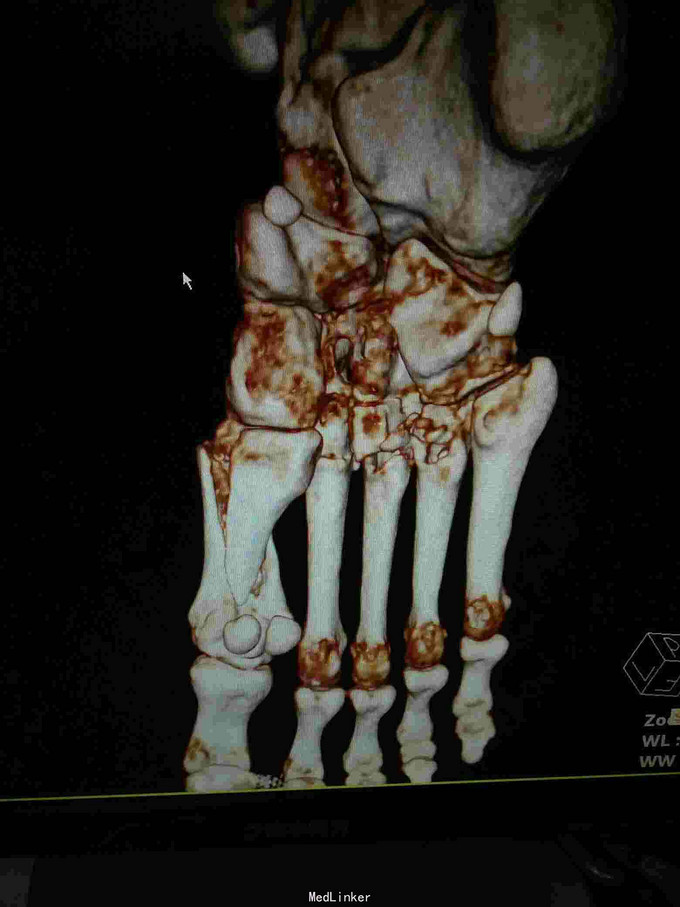

主诉:重物砸伤致右足疼痛伴活动受限2小时; 病史:患者不慎被重物砸伤右足,即感疼痛,活动受限,不能行走,不办皮肤破溃及活动性出血。

查体:右足畸形肿胀,足背少许擦挫伤,无开放性伤口,明显压痛,右足远远端感觉及血运可。 x片:右足第1、2跖骨基底部骨折,第3跖骨基底部可疑骨折; ct:右足第1~4跖骨骨折。

诊断:右足第1、2跖骨粉碎性骨折;右足lisfrance损伤; 治疗:石膏固定,消肿止痛,行右足跖骨骨折切开复位内固定,第1跖骨钢钉及克氏针固定,第2跖骨钢板固定。